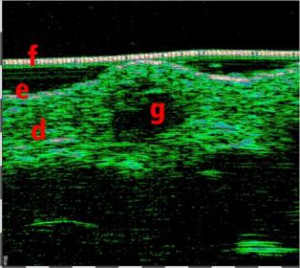

-Υπέρηχος Υψηλής Συχνότητας (HFUS) και Ιστολογία

-Έγχυση Πληρωτικών Υλικών (Fillers)

-Lifting με νήματα